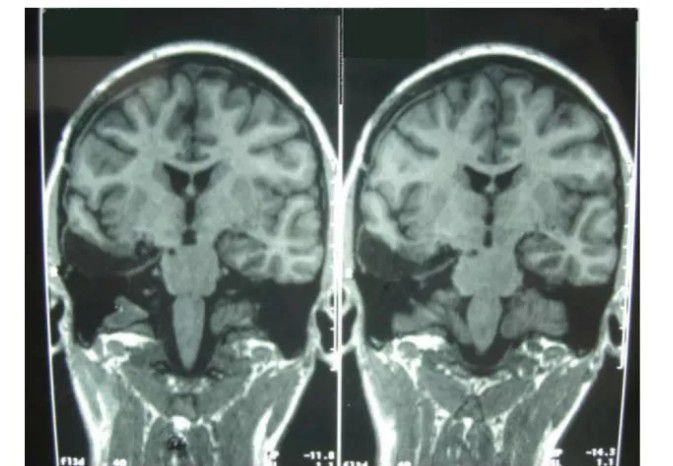

In a strange case, a woman developed "hyper empathy" after having a part of her brain called the amygdala removed in an effort to treat her severe epilepsy, according to a report of her case. The amygdala is involved in recognizing emotions, and removing it would be expected to make it harder rather than easier for a person to read others' emotions, according to the researchers who reported her case, published Aug. 14 in the journal Neurocase. [Image: Patient's MRI Scan after Removing Amygdala] The woman reported experiencing a new, spectacular emotional arousal and feeling physical effects along with her emotions, such as a "spin at the heart" or an "esophageal unpleasant feeling" when experiencing sadness or anger. The researchers evaluated her psychological condition and found she performed exceptionally well on standard tests of empathic abilities. The researchers said that perhaps, even though the amygdala was gone, other brain regions and newly organized connections among them, were responsible for driving stronger empathy. By: https://www.livescience.com/37919-oddest-medical-case-reports/3.html#google_vignette